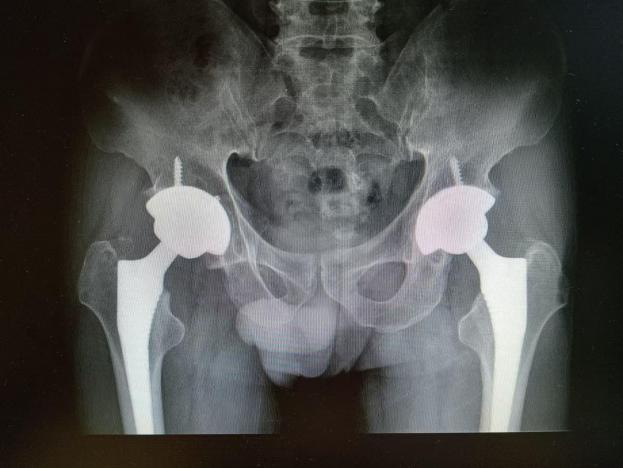

4月23日,贵州航天医院第58次晨读会由我院骨科副主任医师张艳金作学术交流,他以“加速康复指导下的快速手术”为题,详细讲解了老年股骨粗隆间骨折与儿童四肢骨折的临床诊疗难点,结合加速康复外科(ERAS)核心理念,重点阐述了ERAS理念在两大人群中的创新实践,实现患者入院后6至24小时内即可接受手术治疗。针对老年髋部骨折患者,提出通过多学科协作(MDT)与微创手术优化围术期管理,在确保安全前提下缩短术前等待时间,实施精准化麻醉及术后康复方案,可有效降低并发症发生率、改善患者生活质量和预后效果。在儿童骨折领域,强调微创术式与心理干预并行的双轨策略,既减少手术创伤对骨骼发育的影响,同时关注患儿心理疏导,实现生理功能与心理健康同步康复。并通过典型案例的影像学资料与随访数据,直观展示了ERAS理念指导下骨科治疗模式的创新成果。 贵州航天医院骨科 专家简介 赵学平 中共党员,骨科党支部书记、主任,主任医师 临床擅长:从事骨科临床工作30余年,对骨科常见疾病的诊治具有丰富的临床经验。 世界中医药联合会脊柱康复专业委员会常务理事,中华中医药学会整脊分会常务委员,中国中西医结合学会骨伤科分会肢体矫形功能重建与康复专家委员会常务委员,中国研究性医院学会骨科创新与转换专业委员会关节外科学组保髋工作委员会常委,中国康复技术转化及发展促进会骨外科与康复技术转化专业委员会常务委员,泛珠三角区域运动医学联盟(PPRD-SMA)理事会常务理事,中国研究型医院学会运动医学专业委员会委员,贵州省中医药学会整脊分会副主任委员,贵州省中西医结合学会银质针专业委员会副主任委员,贵州省康复医学会骨与关节专业委员会常务委员,贵州省人民医院骨科专科联盟常务理事,贵州省康复医学会骨内科专业委员会常务委员,中华医学会贵州省骨科学会委员,贵州省康复医学会脊柱脊髓专业委员会常务委员,贵州省运动医学分会委员,贵州省康复医学会骨与软组织肿瘤专业委员会委员,遵义市医学会创伤分会副主任委员,贵州省康复医学会骨内科专业委员会遵义地区分会常务委员,遵义市医疗事故鉴定、伤残鉴定、工伤鉴定、司法鉴定专家。 长期从事骨科临床研究及教学工作,在国家级、省部级杂志发表论文20余篇,SCI论文2篇,参与主编骨科专著2部,主持省部级科研项目2项,参与指导省部级、市级科研项目6项。 陈明勇 骨科副主任,副主任医师 临床擅长:从事创伤骨科工作约20年,对骨缺损、骨不连、骨肿瘤、肢体畸形等的肢体矫形重建及功能重建,慢性化脓性骨髓炎的根治治疗、糖尿病足的保肢治疗、快速康复理念(ERAS)下的老年骨折的诊治,四肢复杂骨折的诊治,四肢骨折等微创手术治疗具有丰富的临床经验。 2004年毕业于遵义医学院临床专业,曾在中国人民解放军总医院、广西医科大学第一附属医院、上海第六人民医院骨科进修。中国中西医结合学会骨伤科专业委员会横向骨搬移治疗糖尿病足及微血管网再生学组首届委员,遵义市医学会创伤分会常务委员。 瞿 辉 中共党员,骨科副主任医师 临床擅长:对骨科的常见病、关节外科、脊柱外科及运动医学疾病的诊治具有丰富的临床经验,熟练掌握骨科手术操作技术。 毕业于遵义医学院临床医学系,2005年前往广州中山大学第一附院骨显微医学部进修学习,2011年前往成都华西医院进修学习,并多次在省内外学习骨科相关知识,是中华医学会骨科分会会员。 赵兴东 骨科主任医师 临床擅长:擅长骨科的常见病及各种创伤、四肢骨折创伤修复、骨感染、手足疾病的诊治和手足体表畸形的矫形整复,熟练掌握骨科四肢骨病及创伤的手术操作技术,尤其在四肢关节复杂性损伤、手足外伤、组织缺损创面、难治创面的皮瓣修复方面及平足、高弓足矫形方面及四肢慢性疼痛诊治、康复方面具有丰富的临床经验。 硕士研究生,毕业于遵义医学院临床外科系,2015年前往山东省立医院手足外科进修学习;遵义市医学分会创伤分会第一、二届委员,遵义市手外科医学会第二委届员会常务委员;在省级及省级以上期刊发表文章9篇,参编著作2部,参与主持并完成市级课题1项,参与市级课题2项、省级课题1项。 张艳金 中共党员,骨科副主任医师 临床擅长:从事骨外科工作16年,对复合伤、多发伤的救治、四肢骨干骨折、关节周围骨折、骨肿瘤、骨髓炎等诊治具有丰富的临床经验。 中共党员,硕士研究生,2006年本科毕业于山西医科大学第二临床医学院,2011年研究生毕业于北京军区总医院;在“老年COPD患者合并髋部骨折的诊治”国际合作课题组研究两年,在老年髋部骨折的诊治方面具有丰富的经验,并发表论文6篇;主持遵义市级课题1项,承担遵义医科大学的临床教学工作,获得遵义医科大学优秀带教老师荣誉。编撰有《骨科疾病诊疗精粹》一书,开展2项新技术,编撰地方规范《务川自治县创伤骨科常见疾病诊疗规范》一书。 张俊凯 骨科副主任医师 临床擅长:从事骨科临床工作28年,对创伤骨折、骨感染、骨缺损、骨不连等外科诊治,四肢骨折的微创手术治疗,四肢复杂骨折(如关节内粉碎性骨折、多发骨折等)的损伤控制及手术治疗等具有丰富的临床经验。 1995年毕业于遵义医学院临床专业,2009年前往复旦大学附属医院骨科进修1年。 卢懿明 中共党员,骨科副主任医师 临床擅长:从事骨科工作18年,对创伤骨折、四肢骨折的微创手术治疗、四肢复杂骨折(如关节内粉碎性骨折、多发骨折等)的损伤控制及手术治疗,尤其是髋部骨折的PFNA等微创技术,踝关节骨折、膝关节周围骨折的Mipo微创技术等具有丰富的临床经验,开展了4项新技术,发明6项新型专利技术。 2005年毕业于遵义医学院临床专业,2017年,前往南方医科大学第三附属医院骨科进修半年,回院后运用Mipo技术对骨干骨折及干骺端骨折的治疗技术,同时积极开展骨盆骨折、髋臼骨折腹直肌外侧切口的应用;发表了多篇专业论文,经常参与省内外学术交流会授课,获得医院荣誉称号多个。 邬夏荣 骨科副主任医师 临床擅长:从事骨科工作16年,对四肢复杂骨折、骨肿瘤的诊治,尤其是足踝创伤、慢性踝关节损伤、平足症等诊疗具有丰富的临床经验。 2006年毕业于遵义医科大学临床医学专业,曾在陆军军医大学西南医院进修学习,发表多篇骨科学术论文。 余德怀 中共党员,骨科副主任医师 临床擅长:从事骨科工作10余年,对运动医学、骨关节、脊柱外科常见病、多发病的诊治具有丰富的临床经验。 硕士研究生,2011年毕业于遵义医学院临床医学专业,曾前往遵义医科大学附属医院运动医学专业进修学习;是贵州省医学会运动医学分会青年委员,西部关节镜联盟委员;发表多篇骨科学术论文。 冯 乾 骨科副主任医师 临床擅长:从事骨科工作近20年,熟练掌握骨科多发病及常见病的诊治,尤其对脊柱退变性疾病的诊断及治疗具有丰富的临床经验,主要研究脊柱微创相关治疗方式,能熟练开展椎间孔镜及UBE。 曾前往北京大学第三医院进修学习疼痛及椎间孔镜、首都医科大学友谊医院专业进修脊柱内镜;是贵州省康复医学会第三届脊柱脊髓专业委员会委员;发明专利3项、发表脊柱外科专业论文多篇。 赵小锋 中共党员,骨科副主任医师 临床擅长:从事骨科临床工作11年,对骨科常见病、多发病诊疗有较为丰富的临床经验,擅长脊柱相关疾病诊断及治疗,尤其是颈、腰、腿疼痛疾病诊断及治疗,擅长胸腰椎骨折微创经皮穿刺内固定术、经皮穿刺椎体成形术、经皮穿刺脊柱内镜下腰椎间盘摘除术、单纯开创腰椎间盘摘除术、腰椎滑脱复位椎间植骨椎融合内固定术、腰椎管狭窄减压融合内固定术及人工髋、膝关节置换术等。 2012年毕业于遵义医学院外科学专业硕士研究生,2019年参加“遵义市115医学人才精英计划”于上海交通大学第一附属医院培训学习,2023年于北京大学第三人民医院脊柱外科进修学习,曾获得遵义市优秀医师荣誉称号。 遵义市手外科第一届委员,遵义市医学会创伤分会第一届委员,遵义市医学会创伤分会第二届委员,贵州省康复医学会第三届脊柱脊髓专业会委员,遵义市医学会烧伤与整形外科学分会委员,发表论文5篇,其中国家级核心期刊1篇,SCI论文1篇,主持市级课题1项并结题,参与市级课题2项。 贵州航天医院骨科 简介 基本情况 贵州航天医院骨科组建于20世纪60年代,前身是以创伤和断肢(断指)再植闻名于世的上海市第六人民医院骨科,中国断肢(断指)再植的奠基者、中科院院士陈仲伟等著名专家、学者多次莅临科室指导医疗、教学,是贵州省最早拥有专业骨科技术科室之一,在70年代开展了贵州省首例断肢(断指)再植手术。组建50余年来,诊治患者已逾百万,挽救了无数的伤病员,成为了保障遵义地区人民群众健康的重要支撑。 经过几代人的不懈努力,今天的骨科,已由创伤骨科发展至骨病、骨肿瘤、骨结核等领域,现有脊柱外科、关节外科、四肢创伤、手足外科四个亚专科,成为了集医疗、教学、科研于一体的综合学科,是贵州省临床重点专科、遵义市临床重点专科、遵义市骨科临床医学中心、遵义市基层骨科专科联盟理事长单位。 科室目前开放床位110张,共有医护人员50余人,副高级以上专家18人,硕士研究生15人。拥有一流骨科医疗设备多台,每年不定期选派优秀技术骨干到全国各大知名医学院校进修、学习、参观、交流,并邀请国内、国外知名专家教授来院进行交流、指导,通过不断引进国内外先进的诊疗技术,科室医疗技术水平稳步提升,为广大人民群众提供了优质的医疗服务。 专科特色 骨一科 (一)骨缺损、骨不连的肢体与功能重建 胫骨横向骨搬移技术治疗糖尿病足: (二)慢性骨髓炎的根治治疗 (三)肢体缺血性疾病如糖尿病足、脉管炎的保肢治疗 (四)皮瓣修复 (五)复杂创伤的治疗 (六)老年髋部骨折及小儿骨折快速手术 老年髋部骨折: 骨二科 (一)胸腰椎骨折微创经皮椎弓根螺钉固定术 (二)老年性骨质疏松性患者腰椎滑脱脊柱内固定术(骨水泥螺钉) (三)V形双通道脊柱内镜技术(VBE)腰椎融合术治疗腰椎退行性疾病 (四)老年性骨质疏松性骨折(PVP/PKP)术 (五)人工髋关节置换术 (六)双侧股骨头坏死人工全髋关节置换 (七)右侧全髋置换术后假体周围骨折翻修 (八)人工膝关节置换术 (九)人工膝关节假体松动翻修 (十)关节镜技术 传统手术切口 关节镜技术切口 诊疗范围 骨一科 1.四肢创伤、矫形。 2.手、足踝外科。 骨二科 end